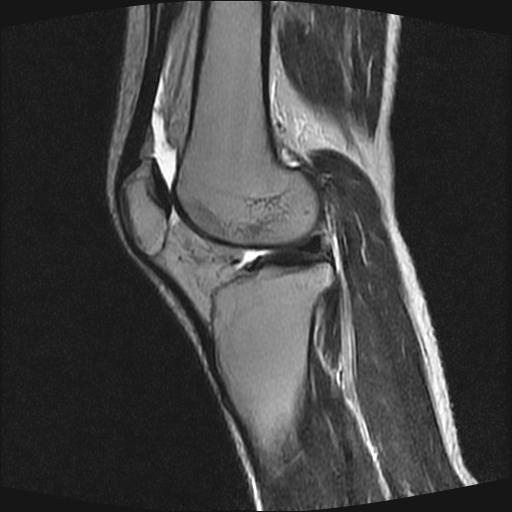

标题: MRI1265:男性40岁,右膝关节 [打印本页]

标题: MRI1265:男性40岁,右膝关节

40岁男性,右膝关节外伤,x光平片示,髁间隆突撕脱骨折。

1、前交叉韧带撕裂;

2、外侧半月板后角撕裂;

3、关节腔积液。

前交叉韧带撕裂,关节腔积液.

半月板1-2级损伤   前交叉韧带撕裂伤   关节腔少量积液  诸骨未见新鲜外伤性改变

髁间隆突撕脱骨折;内侧副韧带损伤。

内侧副韧带撕裂及关节腔积液是肯定的,但是前交叉撕裂确定吗?会不会有容积效应的因素,因为前一张前交叉显示清楚,连续性良好,且较光滑。请问楼主有关节镜支持吗?我们医院也经常有这样的患者,但苦于没有关节镜,而无法对照、证实(除非完全断裂),出现了不同的诊断结果只能毫无意义的争论。

1、前交叉韧、内侧副韧带撕裂;

3、关节腔积液。4、髁间脊撕脱骨折。

除了关节积液外并无韧带撕裂,acl胫侧附着点有2束,正常情况下脂肪信号。此病例应加做压脂像以便观察是否有骨损伤。